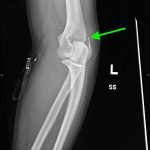

Lateral Epicondyle Fracture

Radiographs of the right elbow revealed an acute fracture through the lateral epicondyle with dislocation of the radial head inferiorly. Radiographs of the left elbow revealed a slightly angulated fracture through the lateral epicondyle.